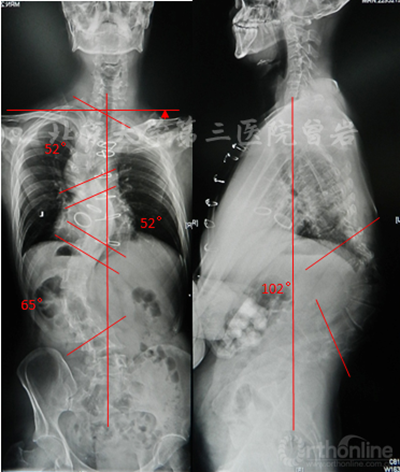

左右Bending X线(图6):左侧Bending上胸弯矫正至46°,胸腰弯矫正至56°;右侧Bending下胸弯矫正至48°。

图6